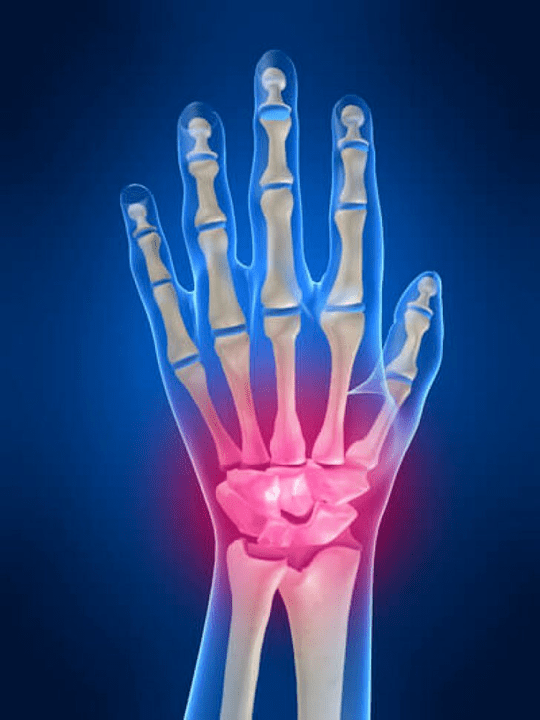

Anatomija zglobova ruke

Svi zglobovi ruke uobičajeni su da se podijele u sljedeće skupine:

- zglob zgloba;

- zglobovi zgloba;

- Zglobovi karpalnog ulaganja;

- Interpencijski zglobovi;

- Parlenalno-falanga zglobovi;

- Interfalanx zglobovi.

Zglob zgloba

Zglob zgloba formira se kostima proksimalnih kostiju (gornji) brojni zglobovi (Triedral, polu -mit, skafoidne kosti) i distalna područja zračenja i kosti lakta. Lakatna kost nije izravno povezana s kostima zgloba, već uz pomoć distalnih (Donji) zglobni disk. Ova struktura odvaja šupljinu zgloba zgloba od distalne šupljine (Donji) Zglob pločica.

Zglobovi zgloba

Zglobovi zgloba predstavljeni su s tri vrste zglobova. Prvi oblik uključuje one zglobove koji se nalaze između kostiju gornjeg dijela (Scaphoid, polu -mit, triedral, grašak -oblikovan) ili donji red (u obliku kuka, glava glava, trapezoidna, hvataljka kostiju). Ti se zglobovi nazivaju međuprostornim zglobovima. Po drugom tipu rangiran je SO -Acled Mid -pisac. Ovaj spoj ima oblik u obliku slova S i formira se zbog spajanja kostiju gornjeg i donjeg retka zgloba. Treća vrsta uključuje spoj graška kosti. Kroz ovaj spoj, triedralna kost je povezana s graškom kosti.

Zglobovi kapecen-penala

Zglobovi karpalnog panela povezuju kosti zgloba i metakarpalnih kostiju. Ti se spojevi formiraju kontaktom proksimalnih krajeva (razbojnici) Metakarpalne kosti i distalni dijelovi karpalnih kostiju koji pripadaju drugom redu. Zglobovi karpalnog uzorka uključuju dva glavna zgloba. Prvi je zglob palca koji igra karpal. Nastaje spojem prve metakarpalne kosti s hvatanjem kostiju.

Drugi je spoj uobičajeni zglob karpalnih staza za ostatak karpalno-sina spojeva između druge, treće, četvrte, pete metakarpalne kosti i trapezoidnih, glavnih kostiju i, djelomično, presjek kostiju. Zglob palca karpalno-uzorke odvojen je od ukupnog zgloba karpalnog uzorka. Zbog kojih su u njemu mogući aktivniji pokreti, u usporedbi s ostatkom karpalnih staza (koji su uključeni u opći zglob karpalne staze) koji se smatraju sjedećim. Zglobovi karpalne ploče ojačani su jakim zglobnim kapsulama, kao i ligamentima (Ligamenti za leđa i dlake).

Tumačeći zglobovi

Bočne površine druge, treće, četvrte i pete metakpalne kosti, kada ih kontaktiraju jedna drugu, formiraju međupromex zglobove. Ovi zglobovi imaju odvojene zglobne kapsule, koje se približavaju kapsulama karpalnih staza, povezane su s njima. Pored kapsula, ovi zglobovi imaju ligamentni aparat predstavljen među -ispitivačima metakarpalnim ligamentima, kao i stražnjim i palmarnim ligamentima. Interpenerske zglobove pripisuju se sjedećim zglobovima ruke, budući da zglobne površine kostiju koje tvore ove spojeve imaju ravan oblik.

Zglobovi parleen-falanga

Parleus-falanx zglobovi su spojevi između distalnih (donji) s krajevima metakarpalnih kostiju i proksimalnih (gornji) Područja prvih falangira prstiju ruku. Svaki prst gornjeg udova ima svoj zglob metakarponalnog zgloba. Dakle, na svakoj ruci nalazi se pet metakarpalnih falansiračkih zglobova.

Interfalange zglobovi

Interpofalanx zglobovi nastaju kombinacijom susjednih falangira svakog od prstiju. Velika (prvi) prst ima samo jedan interfalratirani spoj, jer ovaj prst ima samo dvije falange (proksimalni i distalni). Ostatak prstiju svake od ruku imaju dva zgloba za interfalaciju.

Prvi od njih je lokaliziran između prvog (proksimalan) i drugo (prosječan) prsti i nazvani proksimalne falange (gornji) Interphalang spoj. Drugi tvori vezu između prosjeka (drugi) i posljednje (distalni) Falange prsta. Drugi interfalangealni zglobovi nazivaju se distalnim međufakniranim spojevima. Inter -falanx zglobovi ojačani su kolateralnim i palmanim ligamentima. Ti zglobovi pripadaju blok zglobovima, čiji su pokreti mogući samo oko frontalne ravnine (Borba i savijanje).